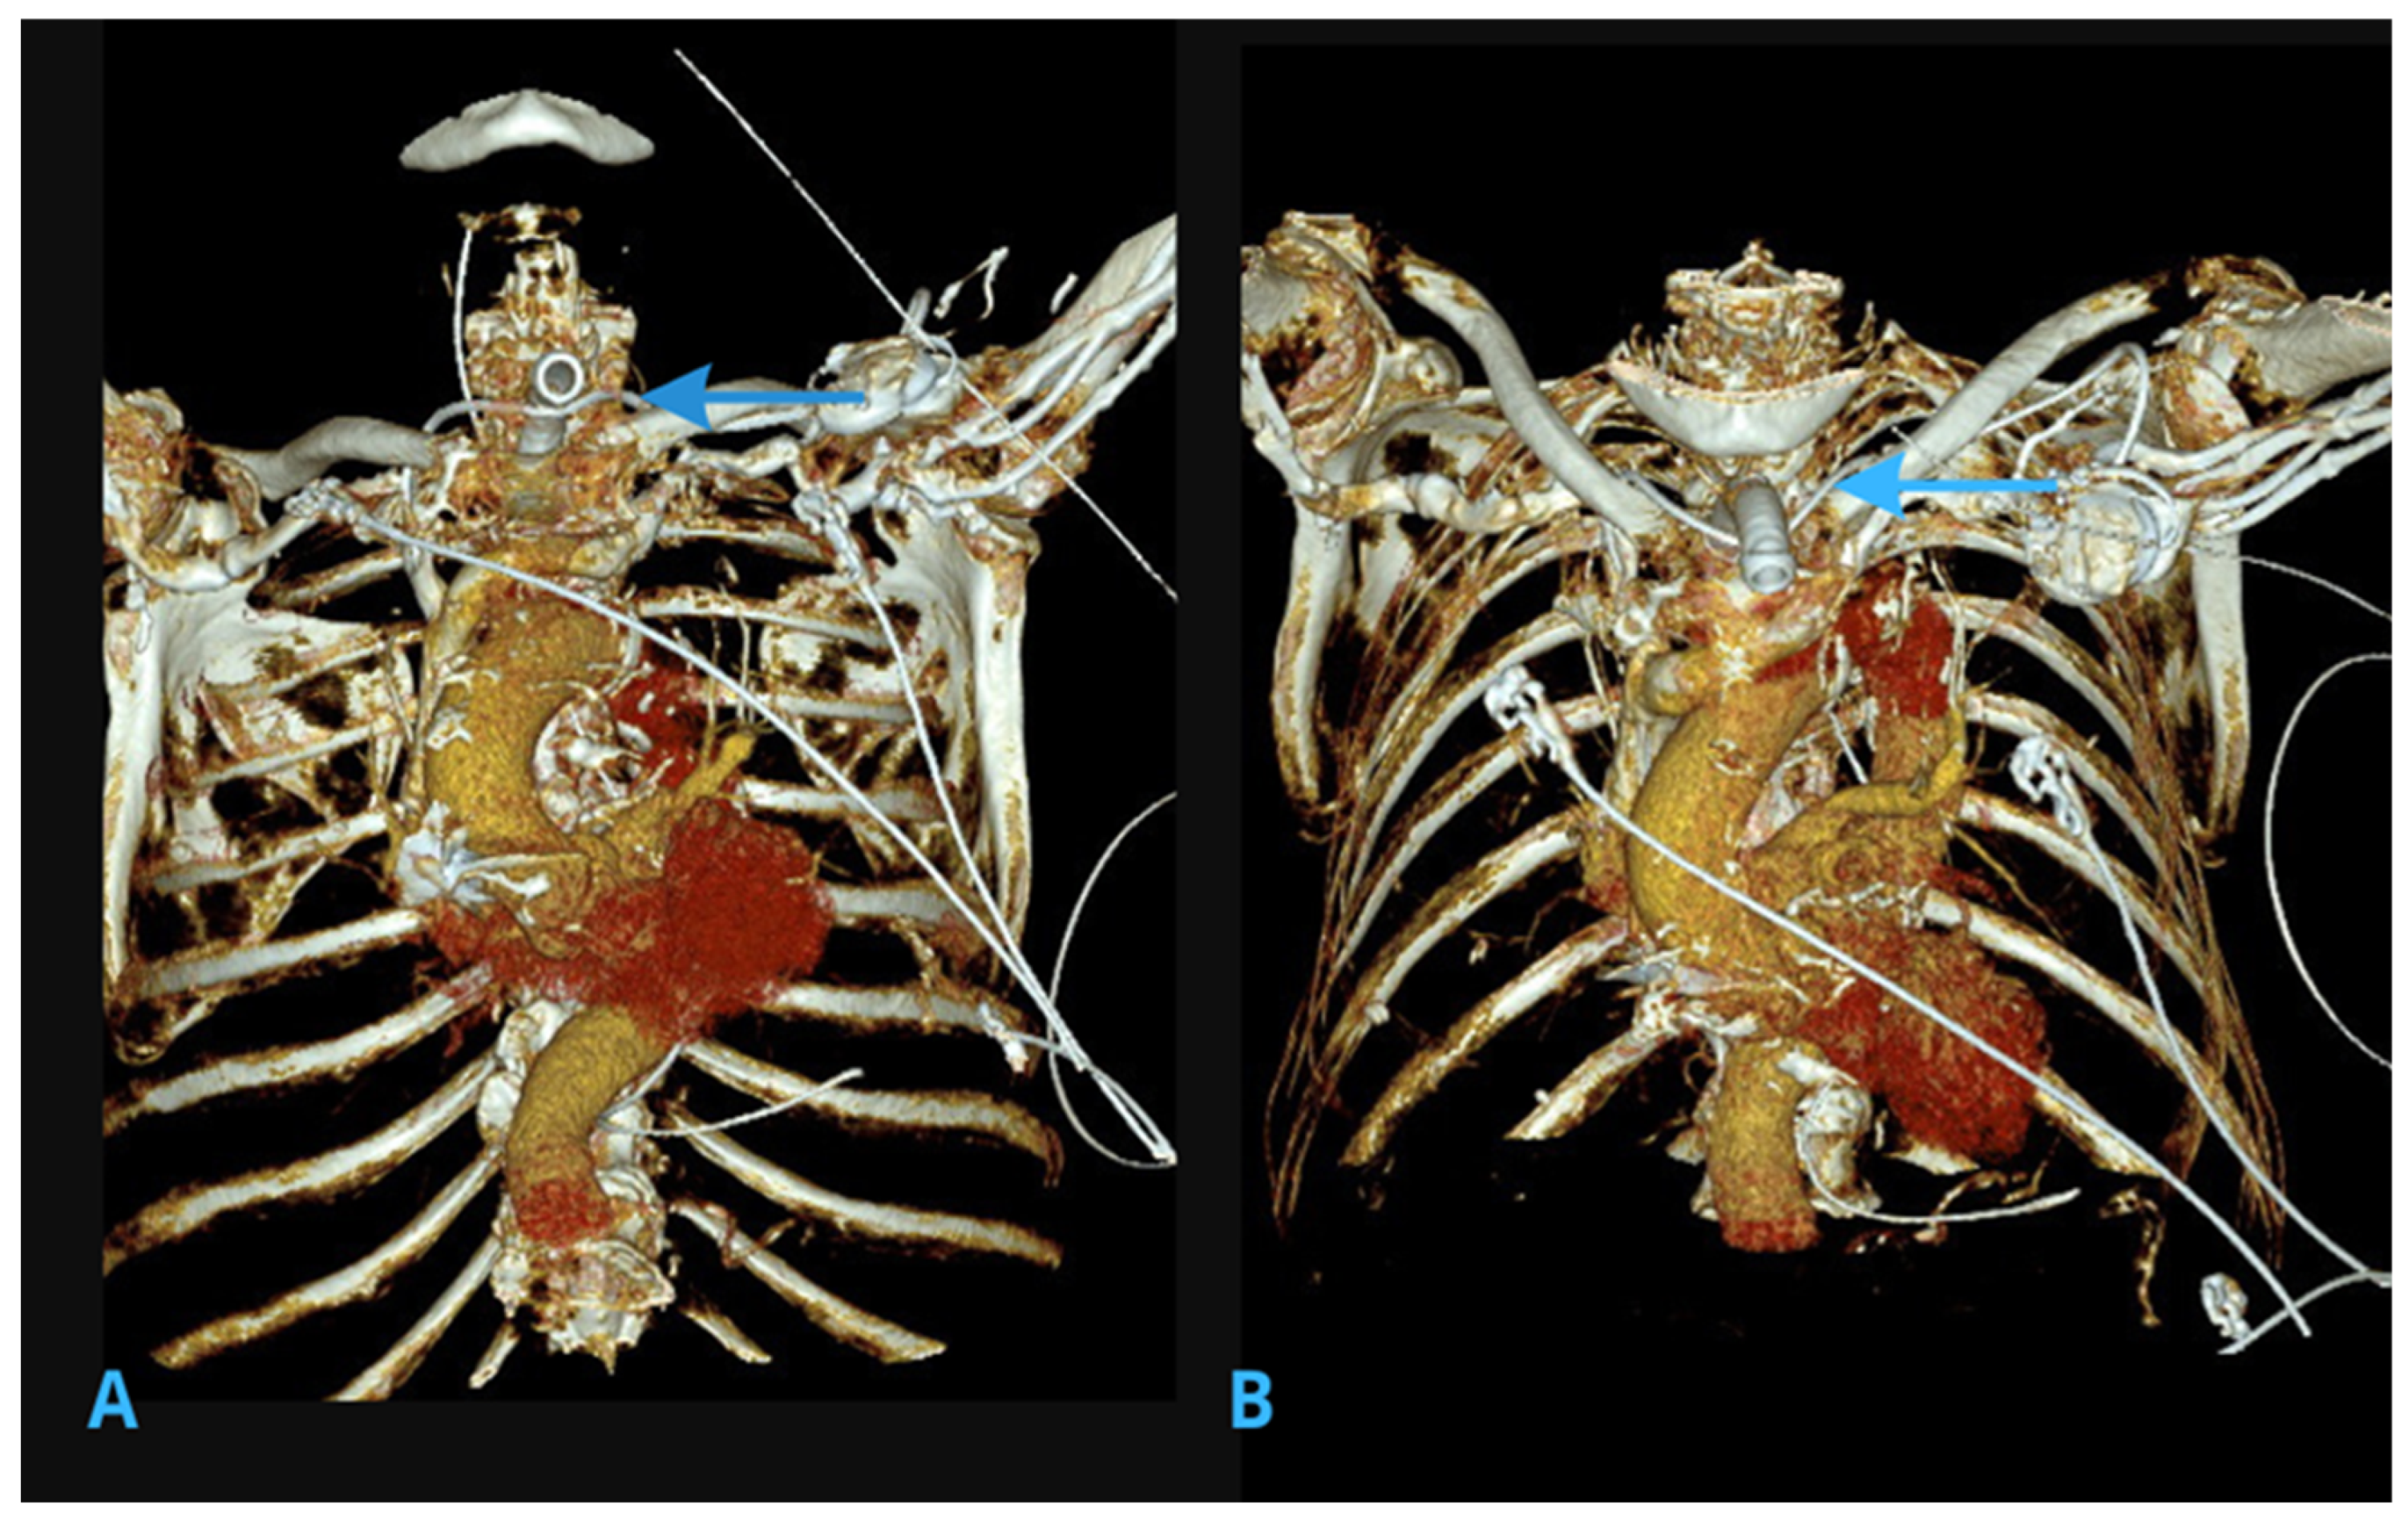

2.2. Computed Tomography (CT) Scans of the Chest